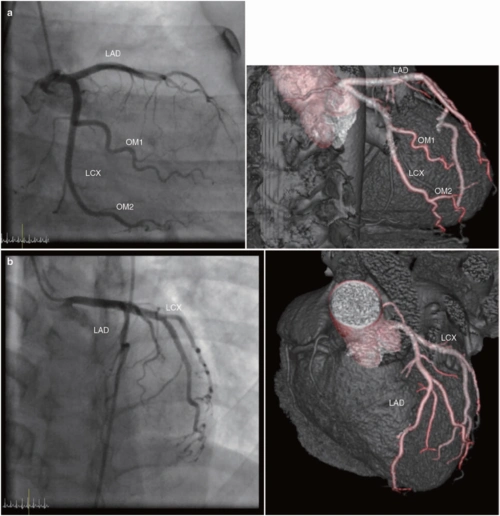

ct和mri如何看正常及异常冠状动脉,高清图谱请收好!